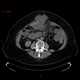

Incisional hernia

An incisional hernia is a type of hernia caused by an incompletely-healed surgical wound. Since median incisions in the abdomen are frequent for abdominal exploratory surgery, ventral incisional hernias are often also classified as ventral hernias due to their location. [Source: Wikipedia ]